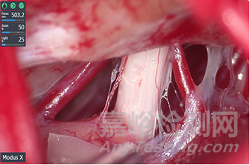

Modus X該平臺(tái)可使用熒光引導(dǎo)手術(shù)能夠?qū)崟r(shí)改善腫瘤組織分化。通過新鏡片進(jìn)行手術(shù),具有4K 3D光學(xué)、27倍放大、自動(dòng)圖像聚焦、語音引導(dǎo)等功能。

Modus X除4K 3D光學(xué)、放大27倍外還具有650mm工作距離,并在98%的手術(shù)沒有背部和頸部疼痛,具有適宜人體使用的設(shè)計(jì)。此外, 與顯微鏡檢查相比,頸部屈曲拉傷所花費(fèi)的時(shí)間減少了24%。

Modus X不在與傳統(tǒng)設(shè)備一樣,使用4K 3D數(shù)字顯示器平視操作,緩解不舒服的視角,便可把操作者從顯微鏡的目鏡上移開。